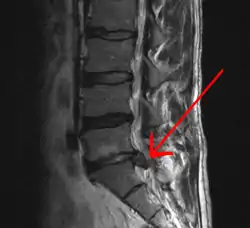

![]() تصوير فتق القرص الفقري من خلال التصوير بالرنين المغناطيسي. تصوير فتق القرص الفقري من خلال التصوير بالرنين المغناطيسي. | |

-التصوير بموجات الرنين المغناطيسي.